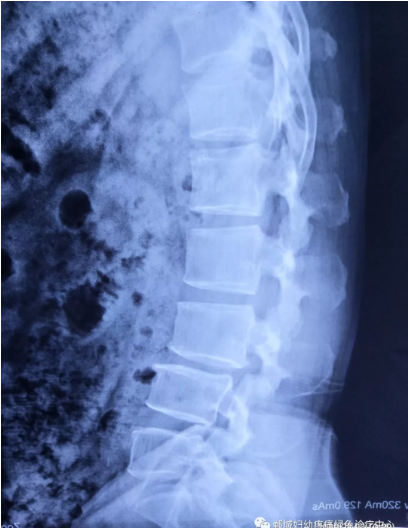

不經(jīng)意間聽(tīng)到有人說(shuō)醫(yī)院疼痛科可以不吃藥不打針,用無(wú)痛苦、無(wú)創(chuàng)傷的方法治療腰痛。陳女士就抱著試試看的心理來(lái)到了鄲城縣婦幼保健院疼痛科,疼痛科時(shí)慶祥主任詳細(xì)了解病情,結(jié)合腰椎磁共振及體征后告訴陳女士她不用手術(shù),通過(guò)腰椎脊柱定位周期減壓牽引系統(tǒng)(外星艙)也能解決腰痛、腰椎滑脫、腰椎反弓這些問(wèn)題。陳女士未曾想到經(jīng)過(guò)十五天的治療后腰部及下肢放射性疼痛癥狀基本消失。陳女士感到十分激動(dòng)與感謝,就在當(dāng)?shù)匦l(wèi)生院做了一個(gè)腰椎正側(cè)位x片和之前的片子作對(duì)比,發(fā)現(xiàn)腰椎滑脫明顯改善。她說(shuō)道:感謝鄲城縣婦幼保健院疼痛科的所有醫(yī)護(hù)人員、感謝外星艙脊柱減壓治好了我的腰痛,也感謝告訴我來(lái)這里的人,她的一句話,讓我省了好幾萬(wàn)元的手術(shù)費(fèi)!

治療后